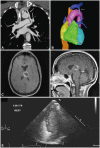

Case report: We present a 47-year-old female with a cryptogenic left thalamic abscess on which Streptococcus mitis grew upon aspiration. Computed tomography of the chest with contrast agent revealed an anomalous connection between the left superior pulmonary and brachiocephalic veins. A right-to-left shunt was confirmed in a transthoracic echocardiogram study in which bubbles were injected into the left arm; this shunt had not previously been noted upon right-arm injection.